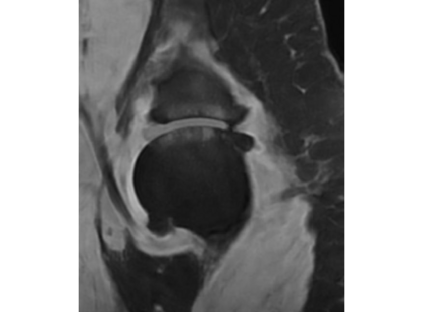

Magnetic resonance (MR) images are often acquired in 2D settings for real clinical applications. The 3D volumes reconstructed by stacking multiple 2D slices have large inter-slice spacing, resulting in lower inter-slice resolution than intra-slice resolution. Super-resolution is a powerful tool to reduce the inter-slice spacing of 3D images to facilitate subsequent visualization and computation tasks. However, most existing works train the super-resolution network at a fixed ratio, which is inconvenient in clinical scenes due to the heterogeneous parameters in MR scanning. In this paper, we propose a single super-resolution network to reduce the inter-slice spacing of MR images at an arbitrarily adjustable ratio. Specifically, we view the input image as a continuous implicit function of coordinates. The intermediate slices of different spacing ratios could be constructed according to the implicit representation up-sampled in the continuous domain. We particularly propose a novel local-aware spatial attention mechanism and long-range residual learning to boost the quality of the output image. The experimental results demonstrate the superiority of our proposed method, even compared to the models trained at a fixed ratio.

翻译:磁共振图像通常在 2D 环境中获得,用于真正的临床应用。通过堆叠多个 2D 切片重建的 3D 体积具有很大的切片间距,导致切片间分辨率低于切片分辨率。超级分辨率是减少3D 图像间隔的有力工具,以便利随后的可视化和计算任务。然而,大多数现有工程都以固定比例对超级分辨率网络进行培训,这在临床场景中不方便,因为MR 扫描的参数各异。在本文中,我们提议建立一个单一的超级分辨率网络,以任意调整比例降低MR 图像的切片间间间距。具体地说,我们将输入图像视为坐标的一个连续的隐含功能。不同间距比率的中间切片可以按照连续域内隐含的显示比例来构造。我们特别提议了一个新的地方觉空间关注机制和远程留置学习,以提高输出图像的质量。实验结果显示我们拟议方法的优越性,即使与所培训的模型相比,也是一种固定比例。